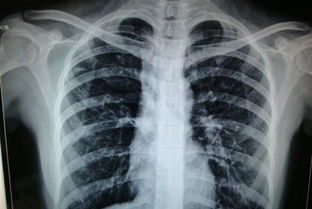

胸透全稱熒光透視,為常用X線檢查方法。它是利用X線具有穿透性、熒光性和攝影效應(yīng)的特性,使人體在熒屏上形成影像,由于人體組織有密度和厚度的差別,當(dāng)X線穿透人體不同組織時(shí),X線被吸收的程度不同,所以到達(dá)熒屏上的X線量就有差異,形成黑白對(duì)比不同的影像,為醫(yī)生的診斷提供依據(jù)。

胸透可以看到胸部的軟組織、骨骼(包括胸椎)、縱隔(心臟、大血管、氣管、食管等)、氣管和支氣、胸膜、肺組織等。可以診斷肺和氣管的先天性疾病,如發(fā)育異常、肺部的各種炎癥、急慢性支氣管炎、比較明顯的支氣管擴(kuò)張癥、肺氣腫或肺水腫、各型肺結(jié)核、肺腫瘤、胸腔積液、氣胸、縱隔腫瘤、心臟形態(tài)異常等

健康查體最常做的是胸部的X線檢查,最基本的就是胸透。 胸透可以看到胸部的軟組織、骨骼(包括胸椎)、縱隔(心臟、大血管、氣管、食管等)、氣管和支氣、胸膜、肺組織等。

可以診斷肺和氣管的先天性疾病,如發(fā)育異常、肺部的各種炎癥、急慢性支氣管炎、比較明顯的支氣管擴(kuò)張癥、肺氣腫或肺水腫、各型肺結(jié)核、肺腫瘤、胸腔積液、氣胸、縱隔腫瘤、心臟形態(tài)異常等。